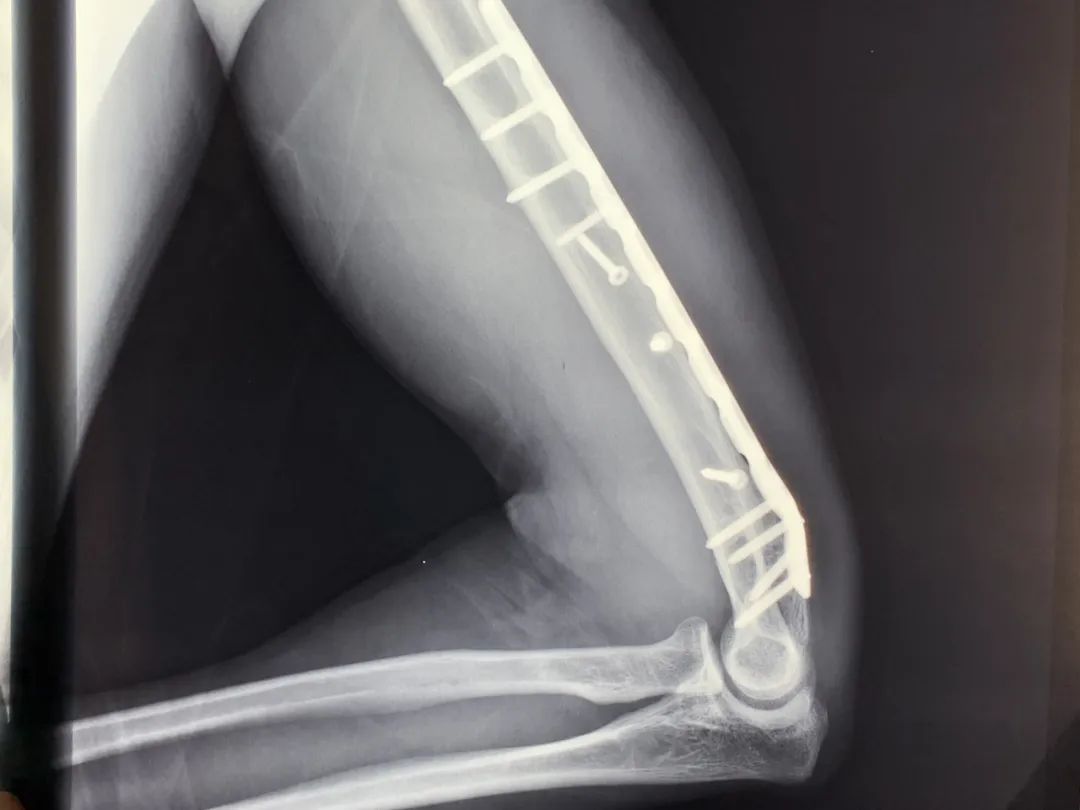

他的右臂肱骨却造成粉碎性骨折

一块23厘米长的钢板和11根钢钉

永远镶在他的右臂里

伴随而来的

还有一张蓝色的残疾人证